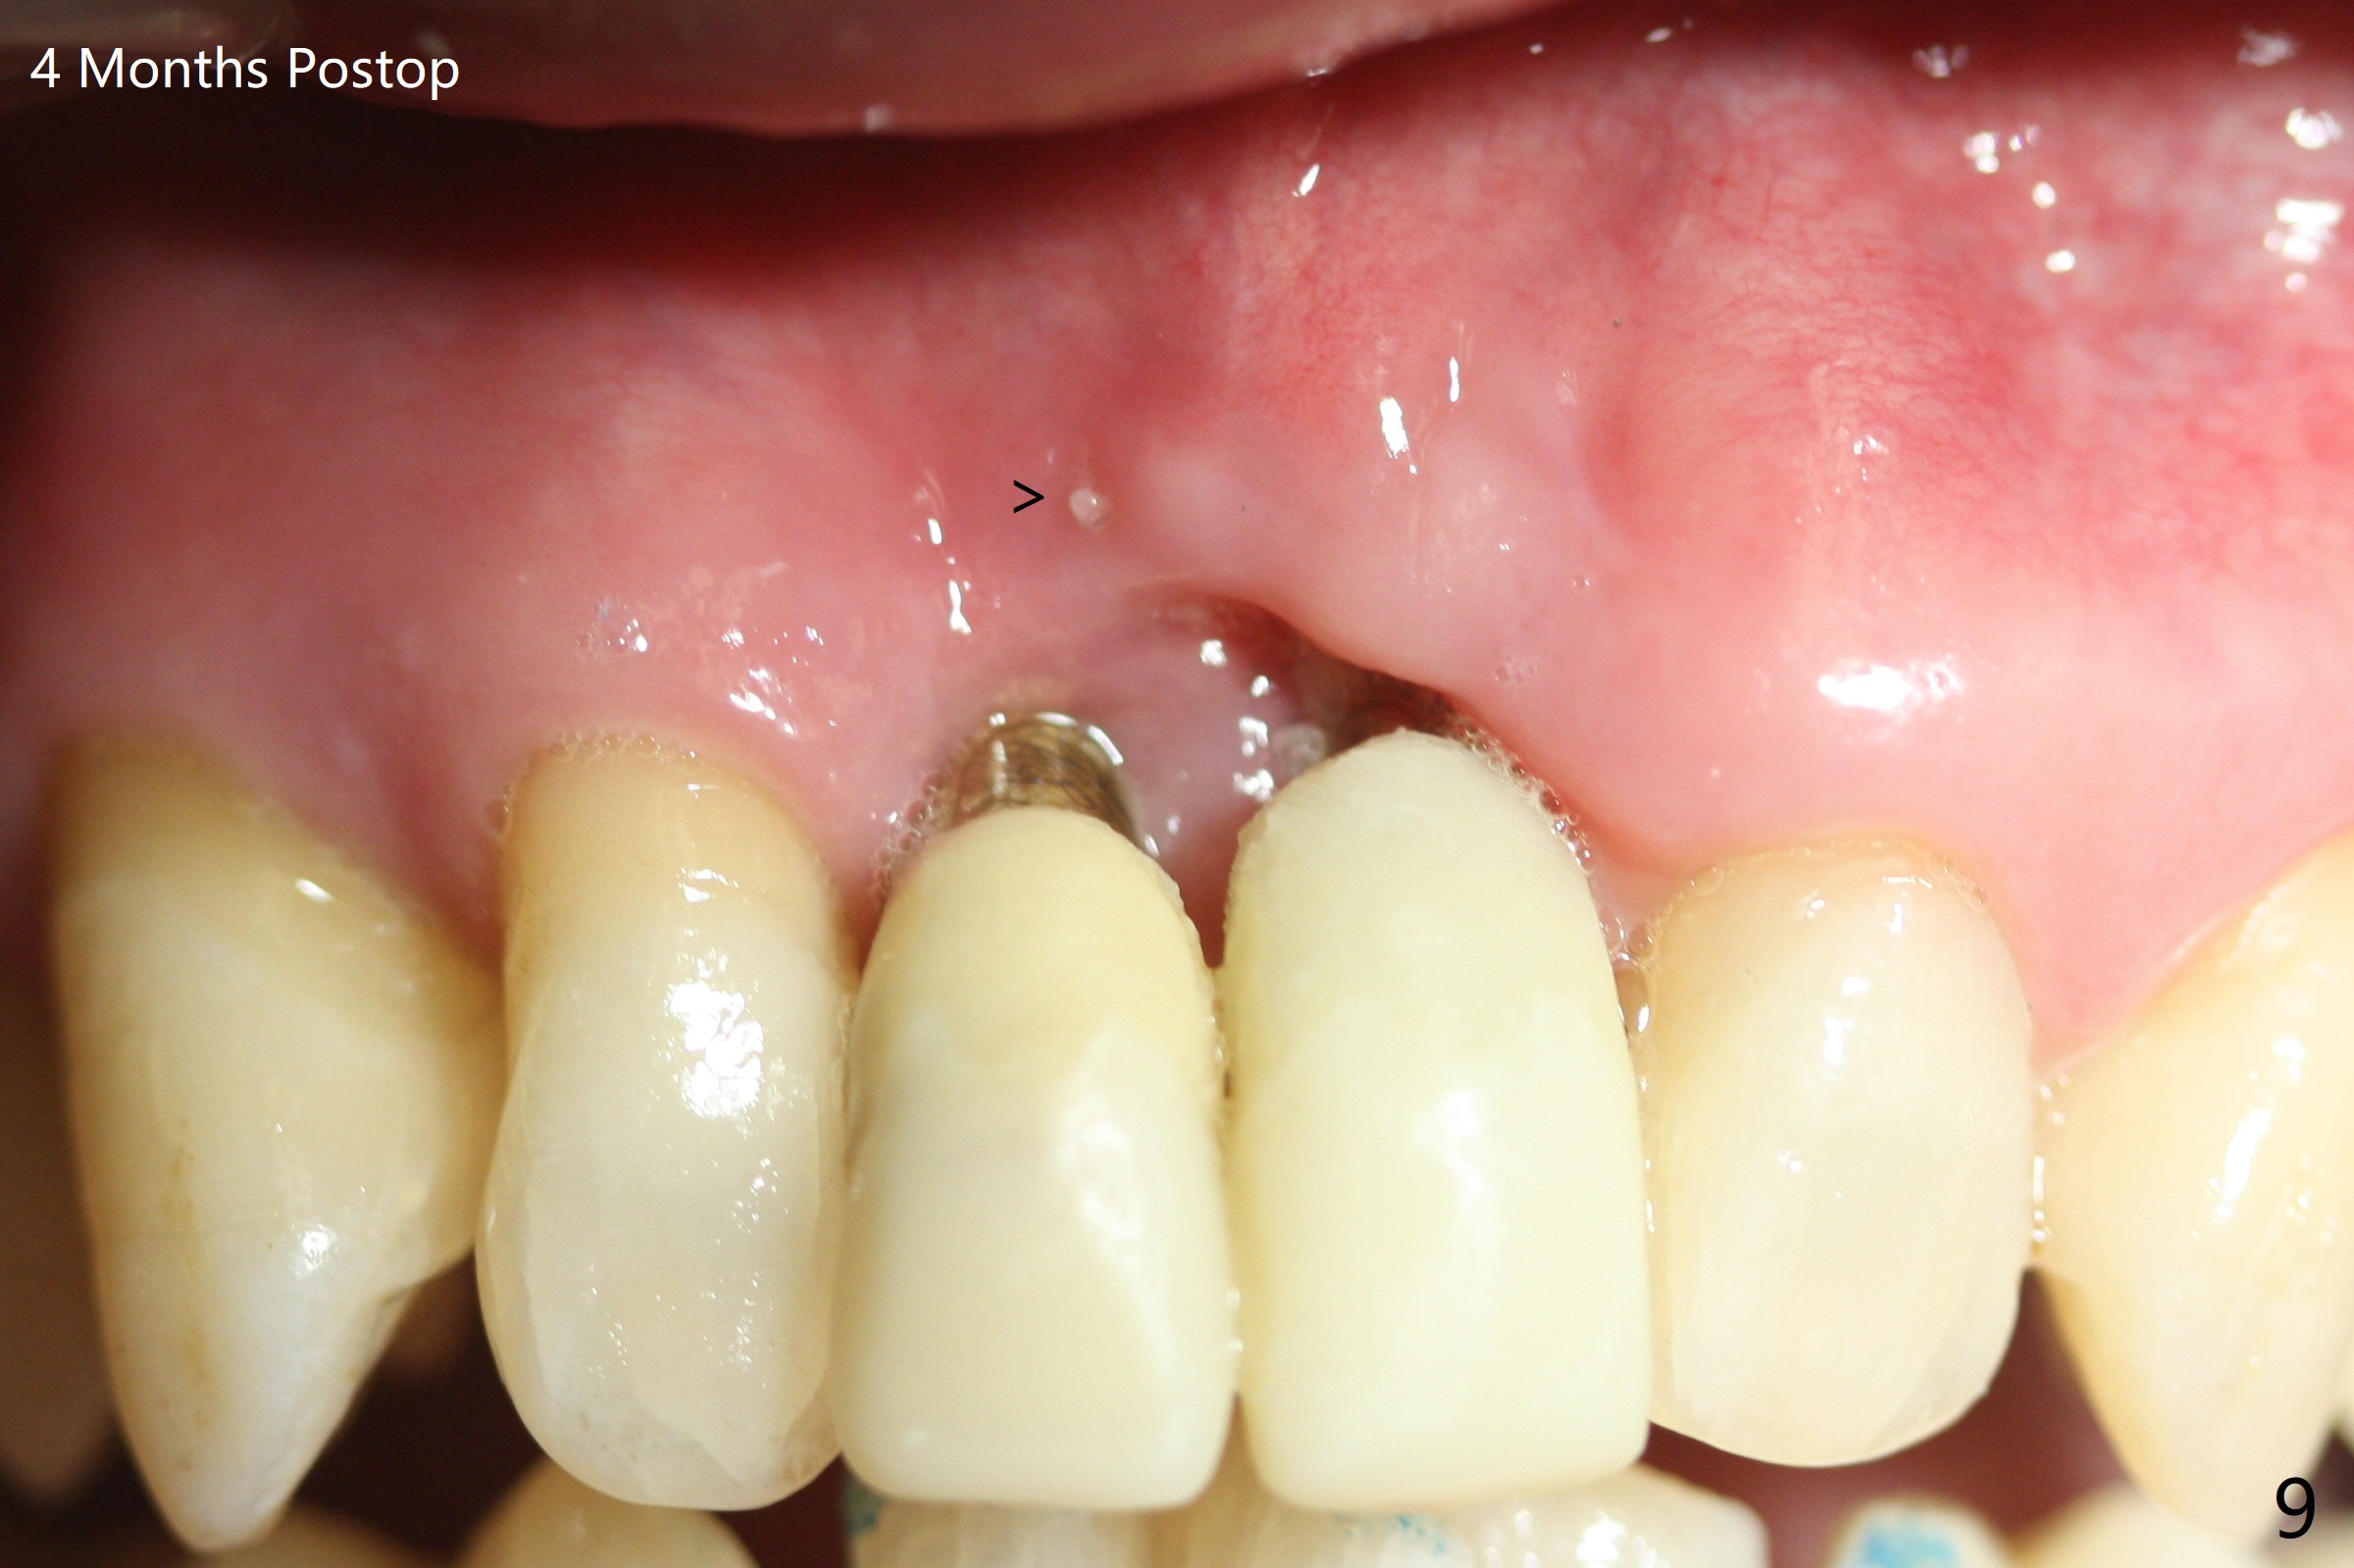

There is no buccal plate at #8 or 9 when the teeth are extracted as well as severe soft tissue defect at #8. Osteotomy is initiated as palatal as possible (Fig.1). When 3.5x13 mm implants are placed initially, the one at #8 is supracrestal (Fig.2 ^). To reduce the chance of peri-implantitis, the implant is placed deeper (Fig.3 (~2 mm implant threads exposed buccally)) with placement of sticky bone around the implants and 4.5x5.5(4) mm abutments (Fig.3 *). The buccal soft tissue defect #8 is repaired with a piece of PRF membrane (Fig.4 *), followed by periodontal dressing. Smaller 2-piece implants (3 mm, IBS) with smaller abutments (4 mm) may further reduce chance of periimplantitis and easy buccopalatal reduction of the abutments for restoration. The periodontal dressing remains stable 7 days postop (Fig.5) because it wraps around the abutments (Fig.6 A). By the time the periodontal dressing gets loose, #8 buccal soft tissue defect should be healing. When breaking-down periodontal dressing is removed 17 days postop, the coronal abutments and bone graft are exposed; after fabrication of provisional crowns (Fig.7), periodontal dressing is re-applied buccally. When the second dressing dislodges 5 weeks postop, the buccal soft tissue appears to reduce (Fig.8). Raising flaps may be less traumatic. A piece of bone graft is being extruded 4 months postop (Fig.9 >). After the abutments change from 4.5x5.5(4) to 4.5x7(3) mm, new temporary crowns are fabricated (Fig.10 (4.5 months postop)). CT shows apparent buccal bone at #8 and 9 (Fig.11,12). How to improve cosmetic?